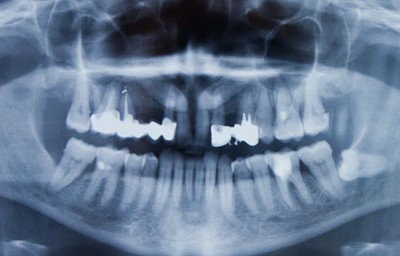

ортопантомограма Ортопантомограмма - это рентгенографический метод исследования зубной полости, в результате которого возможно получить полный панорамный снимок челюстей (верхней и нижней) пациента в фомате 2D. Проведение данной диагностической процедури позволяет оценить состояние зубов и их зачатков, тканей пародонта и костных тканей.

Исследование проводится на специальном рентгенграфическом оборудовании - Ортопантомографе. Аппараты бывают либо пленочными либо цифровыми. Последние имеют возможность значительно снизить дозу необходимого для проведения процедуры излучения, а также значительною большую информативность и оперативность - результаты исследования сразу видны на экране монитора, что позволяет стоматологу мгновенно видеть их и ставить точный диагноз в кратчайшие сроки.

Ортопантомография помогает очень точно оценить расположение зубов мудрости и именно поэтому перед их удалением или лечением рекомендуется провести данное ислледование, хотя бы в целях самостраховки. Кроме зубов на снимке видны, например: нижнечелюстной канал, содержащий сосудисто-нервный пучок, границы челюстных пазух, носовые ходы.